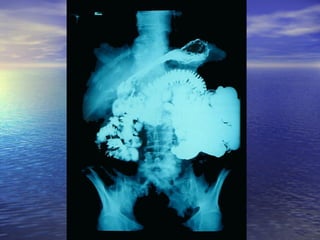

• Estudio radiológico consiste enEstudio radiológico consiste en

administración de 250ml oral de bario y laadministración de 250ml oral de bario y la

obtención de radiografías seriadas delobtención de radiografías seriadas del

intestino, realizadas a intervalos, hastaintestino, realizadas a intervalos, hasta

que el contraste llega al cielo.que el contraste llega al cielo.

Parámetros para analizarParámetros para analizar

• 1.- Calibre de la luz intestinal1.- Calibre de la luz intestinal

• 2.- Contornos Superficie de mucosa2.- Contornos Superficie de mucosa

• 3.- Grosor de la pared de la mucosa3.- Grosor de la pared de la mucosa

• 4.- Desplazamiento de asas4.- Desplazamiento de asas

• 5.- Floculación, segmentación,5.- Floculación, segmentación,

obstrucciónobstrucción (Yeyuno imagen = pluma de(Yeyuno imagen = pluma de

aves)aves)

(ileon imagen = pila de monedas)(ileon imagen = pila de monedas)